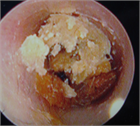

1. 耳閉感を伴う疾患は様々で、患者の訴えも「耳がつまる」以外に「耳がふさがった感じ」「耳の違和感」「音が反響する」「水が入ったような」など多様であるため、初診時の丁寧な問診が重要である(推奨度1)

1. 異物など除去により症状が消失するケースを除き、聴覚検査は診断に必須である(推奨度1)

1. 耳閉感を訴えている症例の中には、耳以外の疾患が原因の場合がある。特に脳血管疾患、腫瘍性疾患など生命予後を左右する鑑別疾患の可能性を想定した場合には、積極的に画像検査を施行する(推奨度1)